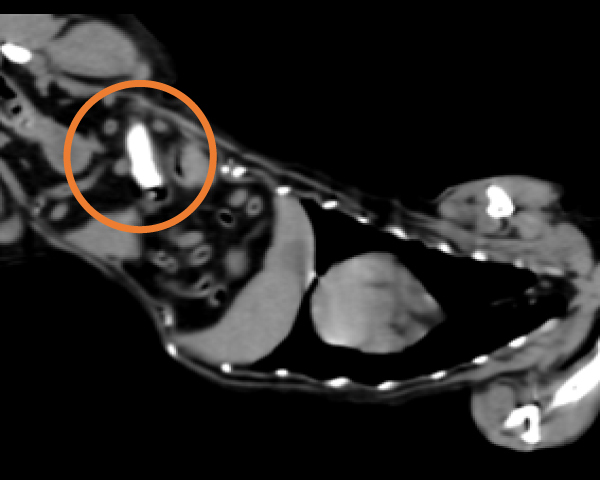

造影CT検査にて腫瘤の浸潤を評価

造影CT検査にて腫瘤の浸潤・転移を評価